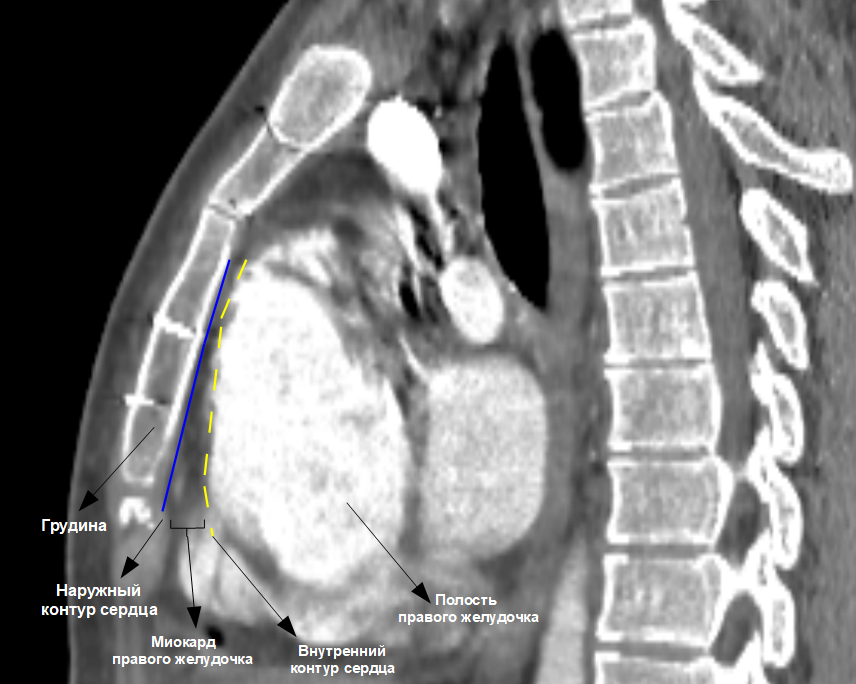

«На этапе завершения операции мы предприняли все необходимые меры для того, чтобы можно было безопасно выполнить следующее кардиохирургическое вмешательство – проложили фрагменты ксеноперикарда (специально обработанные листы (сердечной сумки) перикарда) по передней стенке правого желудочка – область наибольшего прилегания к грудине, отграничив тем самым грудину от сердца. Это позволит минимизировать риски повреждения сердца на этапе выполнении доступа при следующей операции», — комментирует лечащий врач, сердечно-сосудистый хирург Имран Курбанович Исмаил-заде.